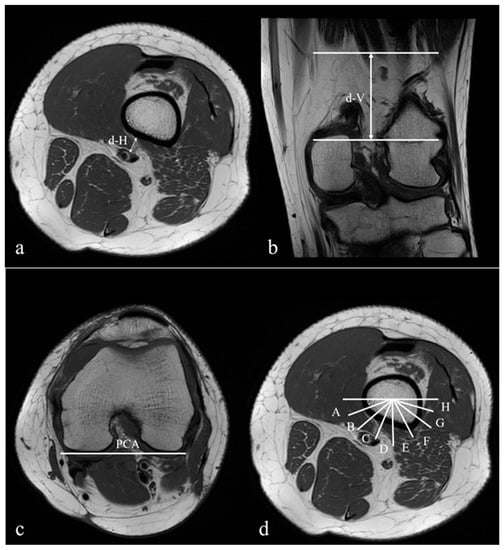

| d-H (mm) | 7.92 ± 3.42 | 6.76 ± 2.86 | 0.010 |

| d-V (mm) | 61.79 ± 9.39 | 51.54 ± 10.49 | <0.001 |